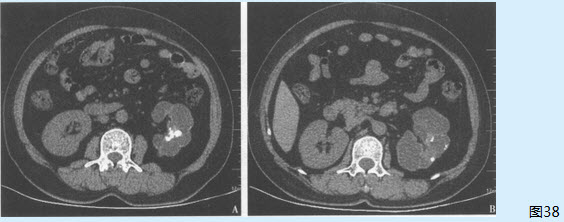

患者男性,28岁,因尿频,尿急,左侧睾丸疼痛3个月就诊。当地医院诊断为慢性前列腺炎,口服左氧氟沙星1个月,症状略好转。现因病情反复来诊。查体:左侧附睾可触及黄豆大小包块。尿常规:白细胞15个/HP,红细胞10个/HP。前列腺液常规:卵磷脂小体50%,白细胞15个/HP。

该患者可能的诊断是( )【提示】患者完善了CT检查(图38)。

图38

• D、左肾结核